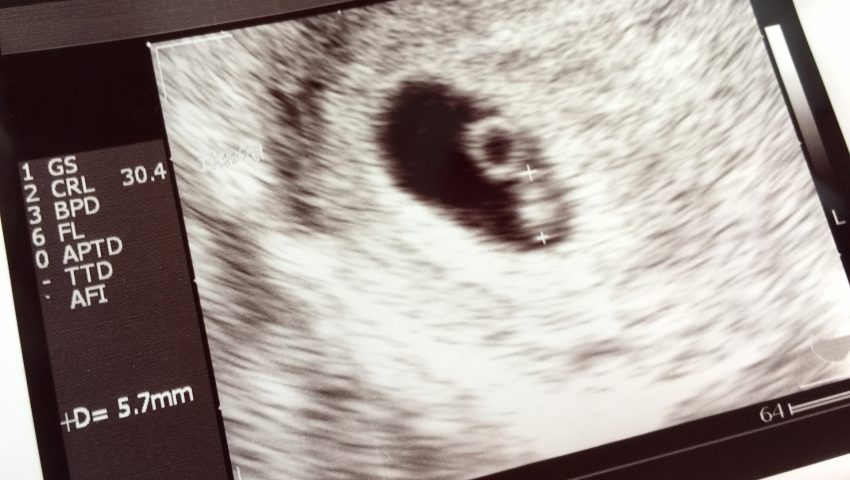

一方、アメリカでは産婦人科は日本より多く、分娩予約も臨月間近(30週頃~)になるまでしません。里帰りが日本ほどメジャーではないアメリカでは、どのような理由で転院しているのでしょうか。